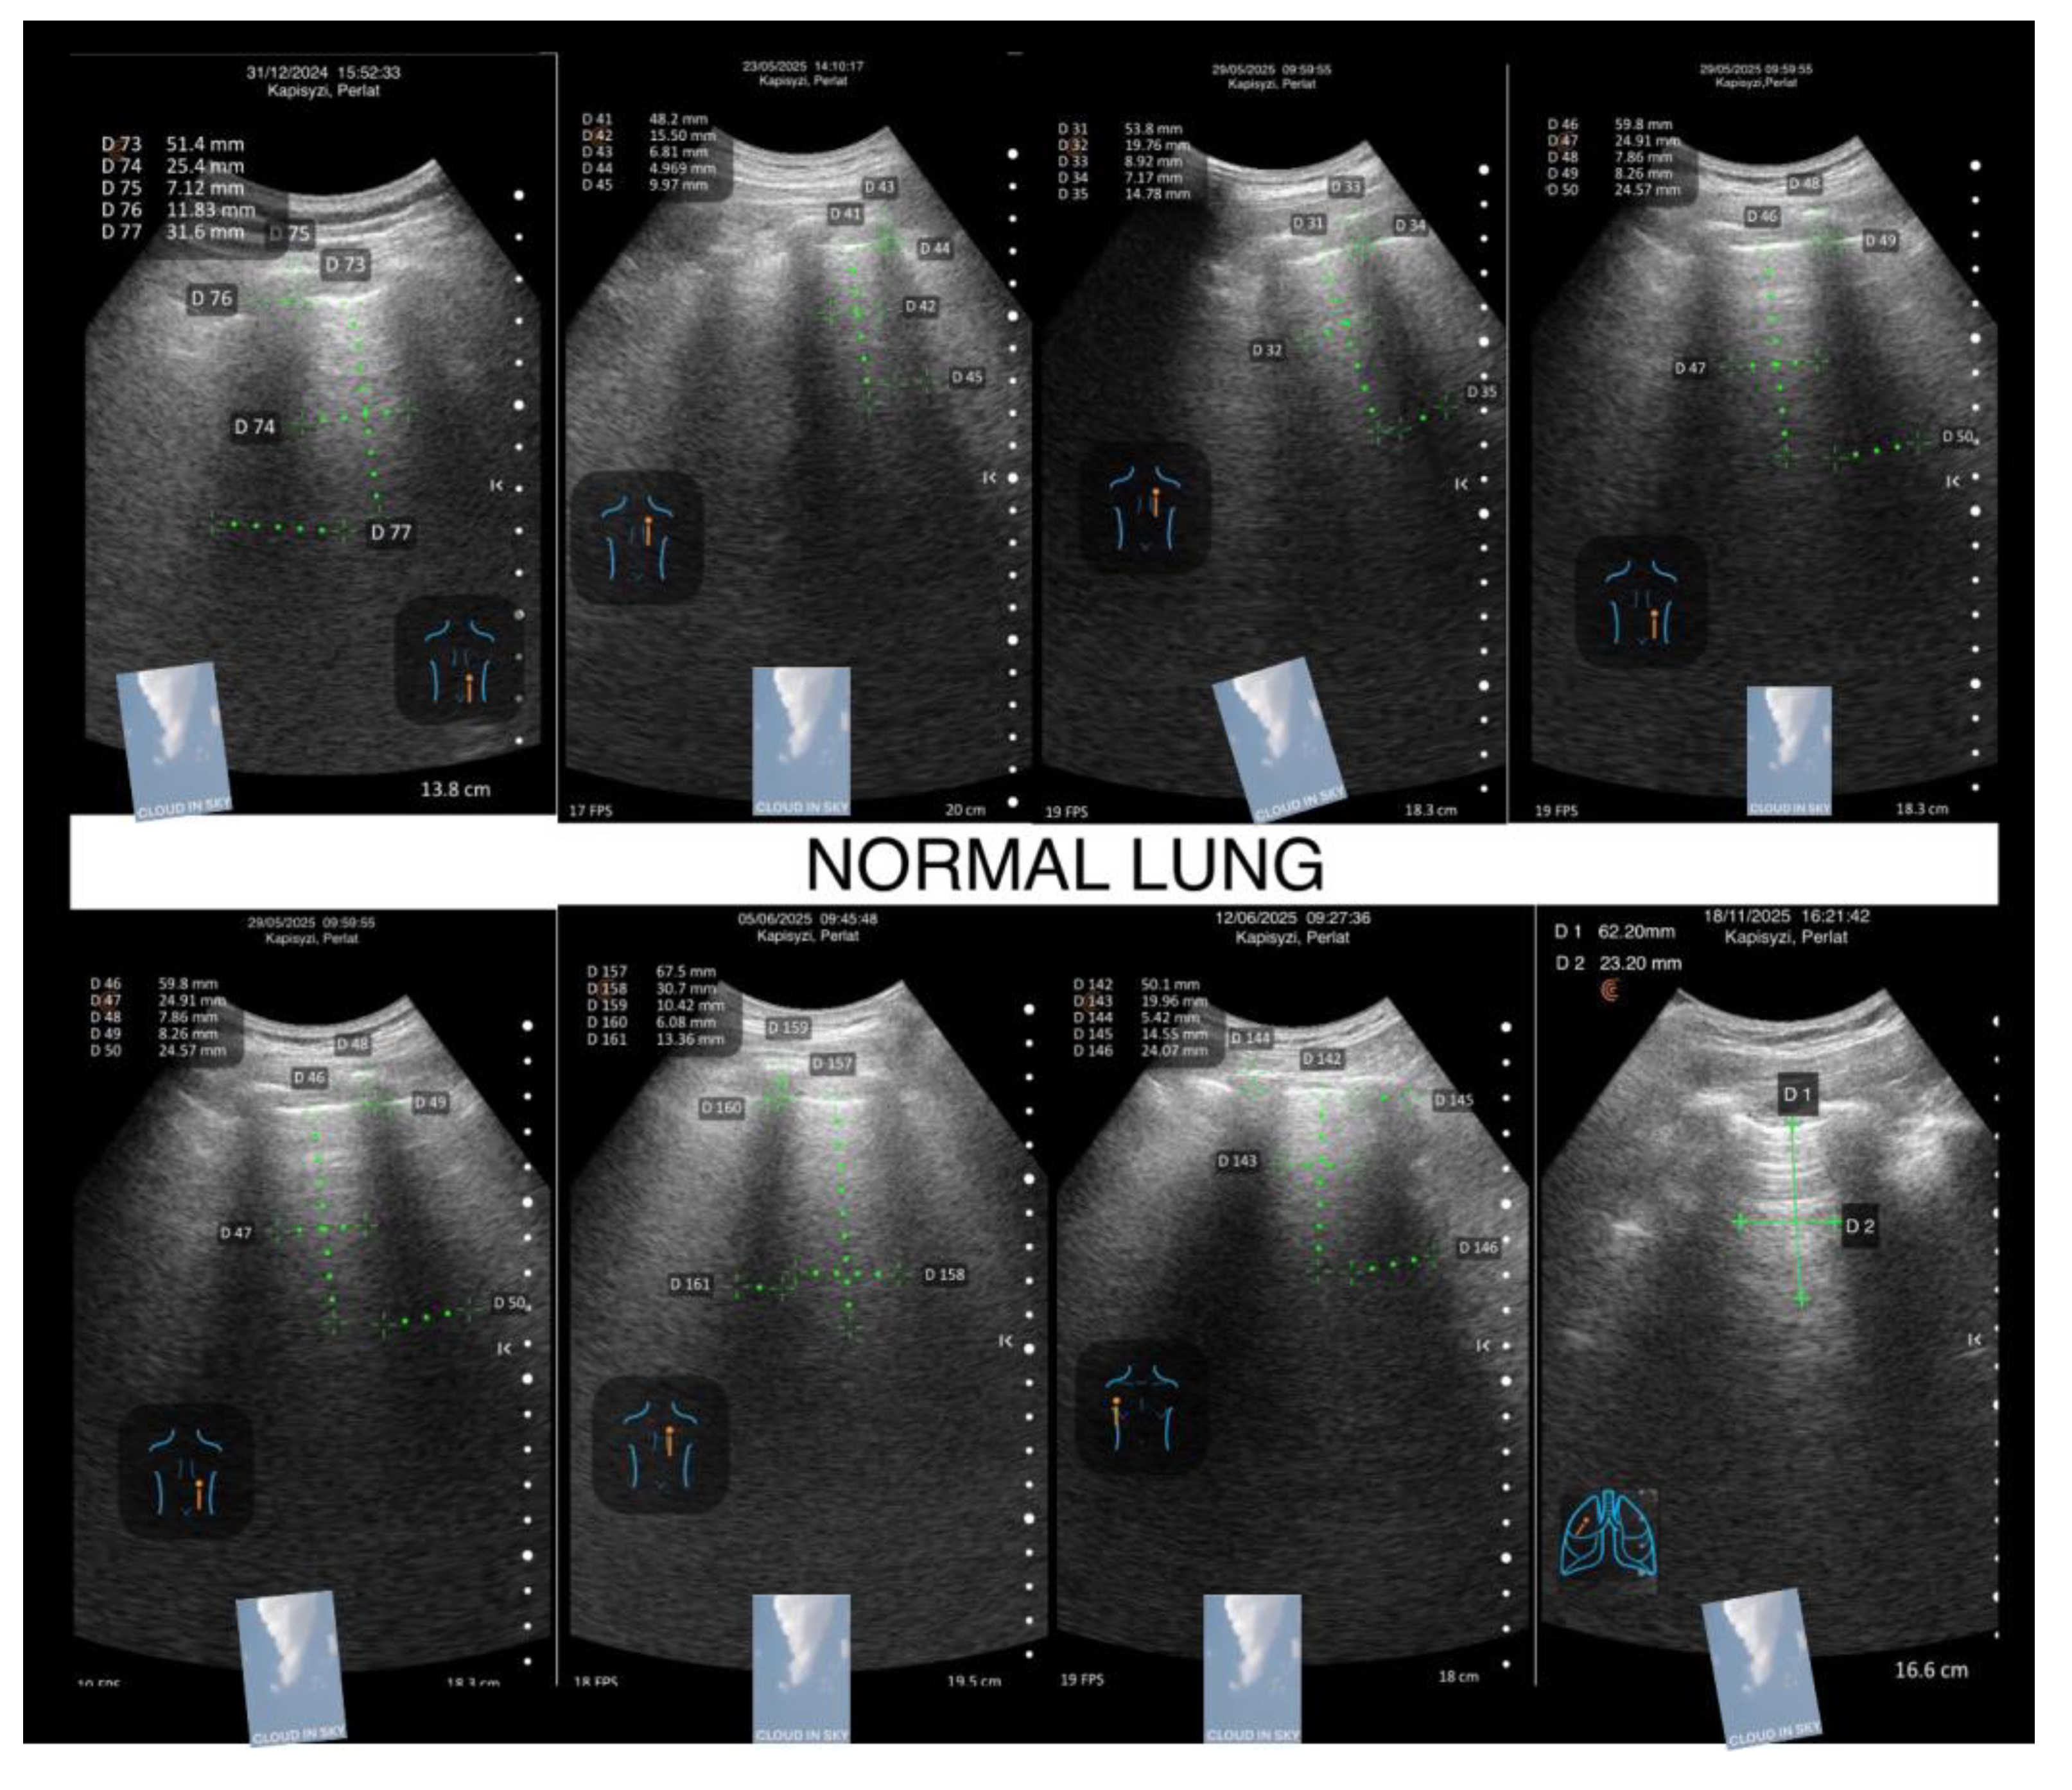

Normal Lung – Geometric Equilibrium and Stable Reflective Pattern (“Cloud in a Clear Sky Pattern”)

The normal lung sets the archetype for comparison.

Its TWA demonstrates:

• balanced width-to-length proportions,

• clean, symmetric transitions into the rib shadows,

• crisp but gentle margins,

• stable brightness without diffusion,

• and coherent geometry expressing intact pleural integrity and physiologic aeration.

This appearance is neither exaggerated nor attenuated; it is structurally harmonious, representing the healthy interaction between the pleural layers and the subpleural microarchitecture.

Visually, it resembles a white cloud in a clear sky—defined, bright, and suspended in a stable environment.

This equilibrium becomes the baseline atmospheric state from which deviations toward nightfall (compression) or foggy dawn (elongation) are immediately perceivable to the informed eye.

(Figure 9: Cloud in a clear sky pattern)

Figure 1. Merlin space, twinkling white area. Kapisyzi, P. ©.

Figure 9. Cloud in a clear sky pattern.